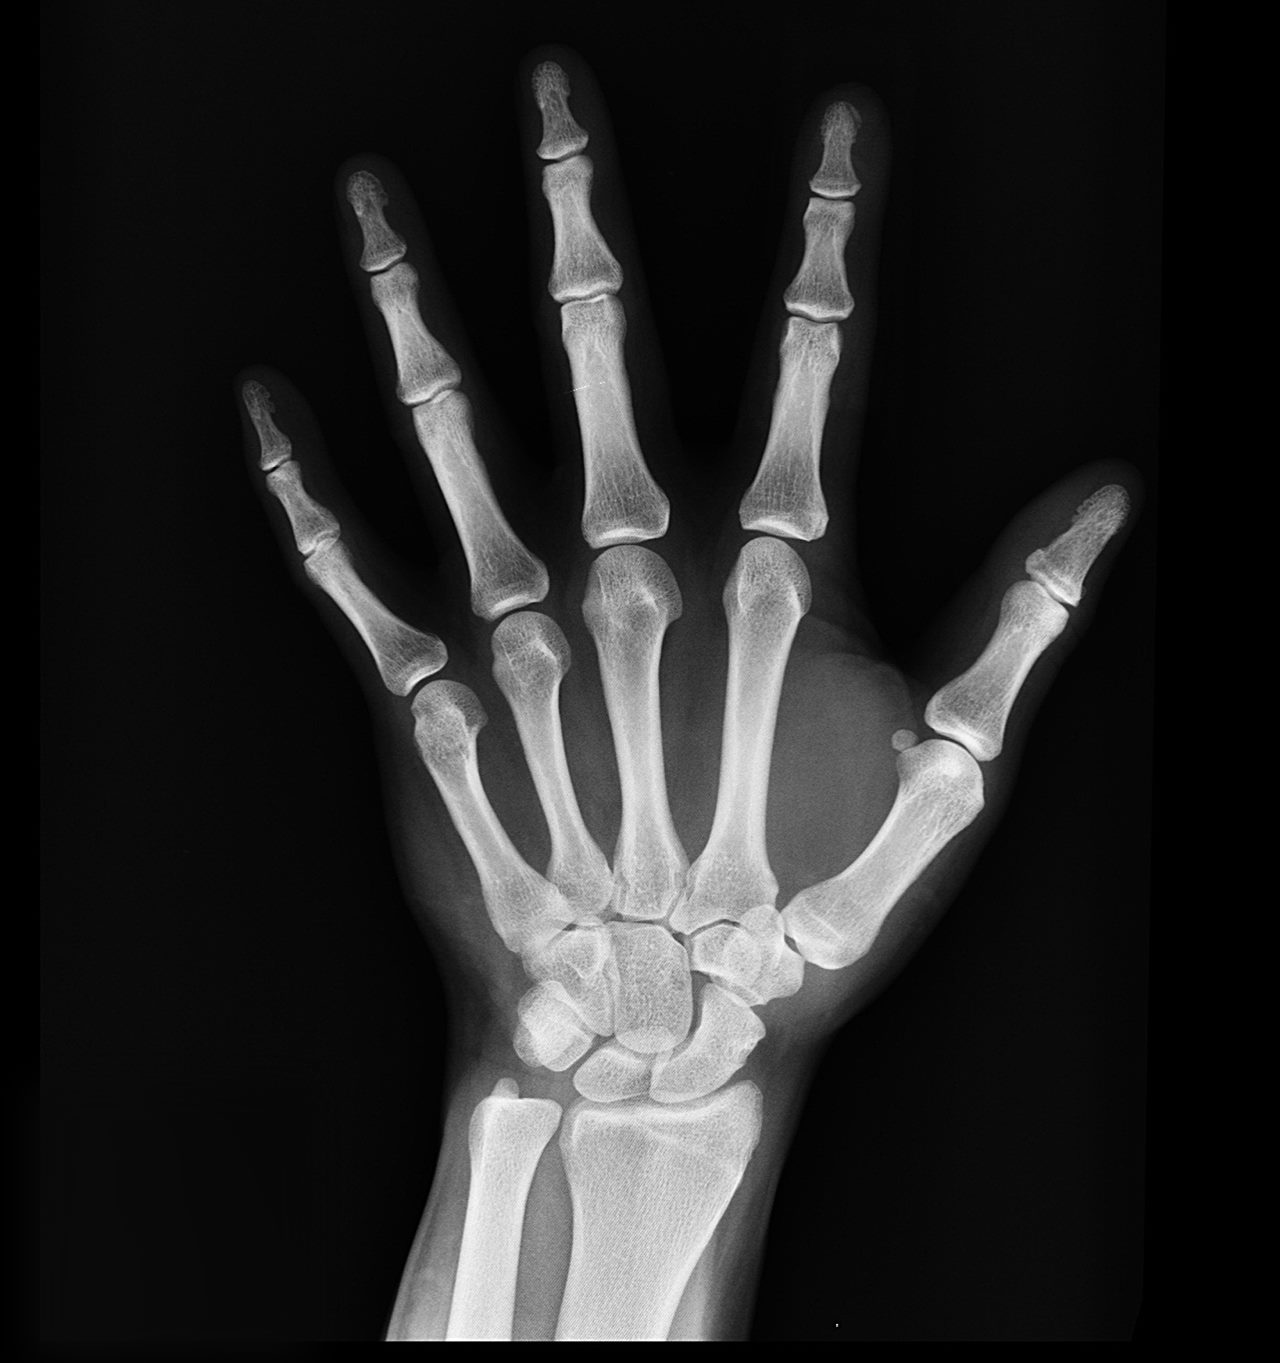

건강한 뼈의 중요성

건강한 뼈를 유지하는 것은 삶의 건강과 복지에 필수적입니다. 튼튼한 뼈의 중요성에 대해 말씀드리겠습니다. 뼈는 몸을 구조적으로 지지하고 우리가 서고, 걷고, 움직일 수 있도록 도와줍니다. 또한 뇌, 심장 및 폐와 같은 필수 장기를 보호합니다. 골수는 산소를 운반하고 감염과 싸우는 데 필수적인 적혈구와 백혈구를 생산하는 역할을 합니다. 뼈는 근육 기능, 신경 신호 및 기타 중요한 신체 기능에 필수적인 칼슘의 저장 장소 역할을 합니다. 건강한 뼈를 유지하면 골절 및 기타 건강 문제의 위험을 증가시킬 수 있는 골다공증과 같은 뼈 관련 질환을 예방할 수 있습니다. 강하고 튼튼한 뼈는 개인이 독립성을 유지하고 제한 없이 즐기는 활동에 참여할 수 있도록 하여 삶의 질을 향상할 수 있습니다. 적절한 영양 섭취, 규칙적인 운동 및 기타 생활 습관을 통해 건강한 뼈를 유지하기 위한 조치를 취하면 개인이 최적의 건강을 유지하고 뼈 관련 상태를 예방하는 데 도움이 될 수 있습니다. 나이가 들어감에 따라 우리의 뼈는 자연스럽게 밀도를 잃기 시작하고 약해집니다. 이 과정은 뼈 손실 또는 골다공증으로 알려져 있습니다. 나이가 들어감에 따라 뼈가 약해지는 이유에 대해 말씀드리겠습니다. 골밀도 감소하는 이유가 있습니다. 나이가 들어감에 따라 우리 몸은 뼈의 강도를 유지하는 데 필요한 칼슘 및 비타민 D와 같은 필수 영양소를 흡수하고 활용하는 능력이 떨어질 수 있습니다. 에스트로겐 및 테스토스테론과 같은 호르몬 변화도 뼈 손실에 기여할 수 있습니다. 특히 여성은 폐경기에 에스트로겐 수치의 감소로 인해 뼈 손실이 가속화될 수 있습니다. 신체 활동 부족은 뼈에 가해지는 스트레스의 양을 줄임으로써 뼈 손실에 기여할 수 있으며, 이는 골밀도 감소로 이어질 수 있습니다. 칼슘과 비타민 D와 같은 필수 영양소가 부족한 식단은 뼈 손실에 기여할 수 있습니다. 코르티코스테로이드의 장기 사용, 갑상선 질환 및 영양 흡수에 영향을 미치는 위장 장애를 포함하여 특정 약물 및 건강 상태도 뼈 손실에 기여할 수 있습니다. 유전적 요인은 뼈의 건강과 골다공증과 같은 뼈 관련 질환에 대한 감수성에 중요한 역할을 할 수 있습니다. 어느 정도의 뼈 손실은 노화 과정의 자연스러운 부분이지만 개인이 더 이상의 뼈 손실을 늦추거나 예방하기 위해 취할 수 있는 조치가 있습니다.